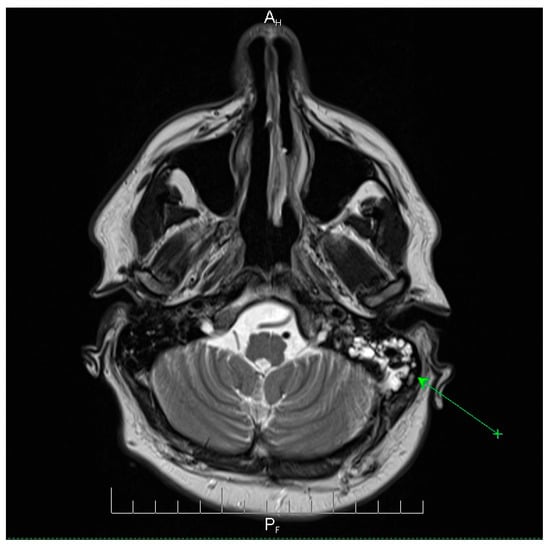

Fulminant Multidrug-Resistant Streptococcus pneumoniae Meningoencephalitis After Elective ENT Surgery: A Case Report

by Corina-Ioana Anton, Madalina Maria Zamfir, Alexandru Ghiță and Mihaela Raluca Mititelu

Pneumococcal meningoencephalitis is a severe infection associated with high morbidity and mortality. Although typically community-acquired, postoperative cases following elective ENT surgery are exceedingly rare. Antimicrobial resistance (AMR) among Streptococcus pneumoniae further complicates management, and missed opportunities for vaccination represent preventable risks. We report a case of a 41-year-old man with multiple comorbidities who developed fulminant S. pneumoniae meningitis 48 h after septoturbinoplasty. The clinical course was atypical, with altered consciousness but no classical meningeal signs, necessitating urgent intubation and intensive care admission. Cerebrospinal fluid cultures identified an MDR pneumococcal strain resistant to penicillin and macrolides but susceptible to vancomycin and meropenem. Empirical therapy with vancomycin and meropenem, combined with adjunctive corticosteroids and multidisciplinary ICU care, led to complete neurological recovery. This case highlights a rare but life-threatening postoperative complication and underscores two critical lessons. First, the growing challenge of multidrug-resistant pneumococcus requires timely recognition, aggressive empiric therapy, and access to effective agents. Second, the absence of pneumococcal vaccination in this high-risk surgical patient illustrates a preventable gap in care. Integrating vaccination screening into preoperative evaluations may reduce the risk of catastrophic postoperative CNS infections. Full article

Show Figures

Figure 1